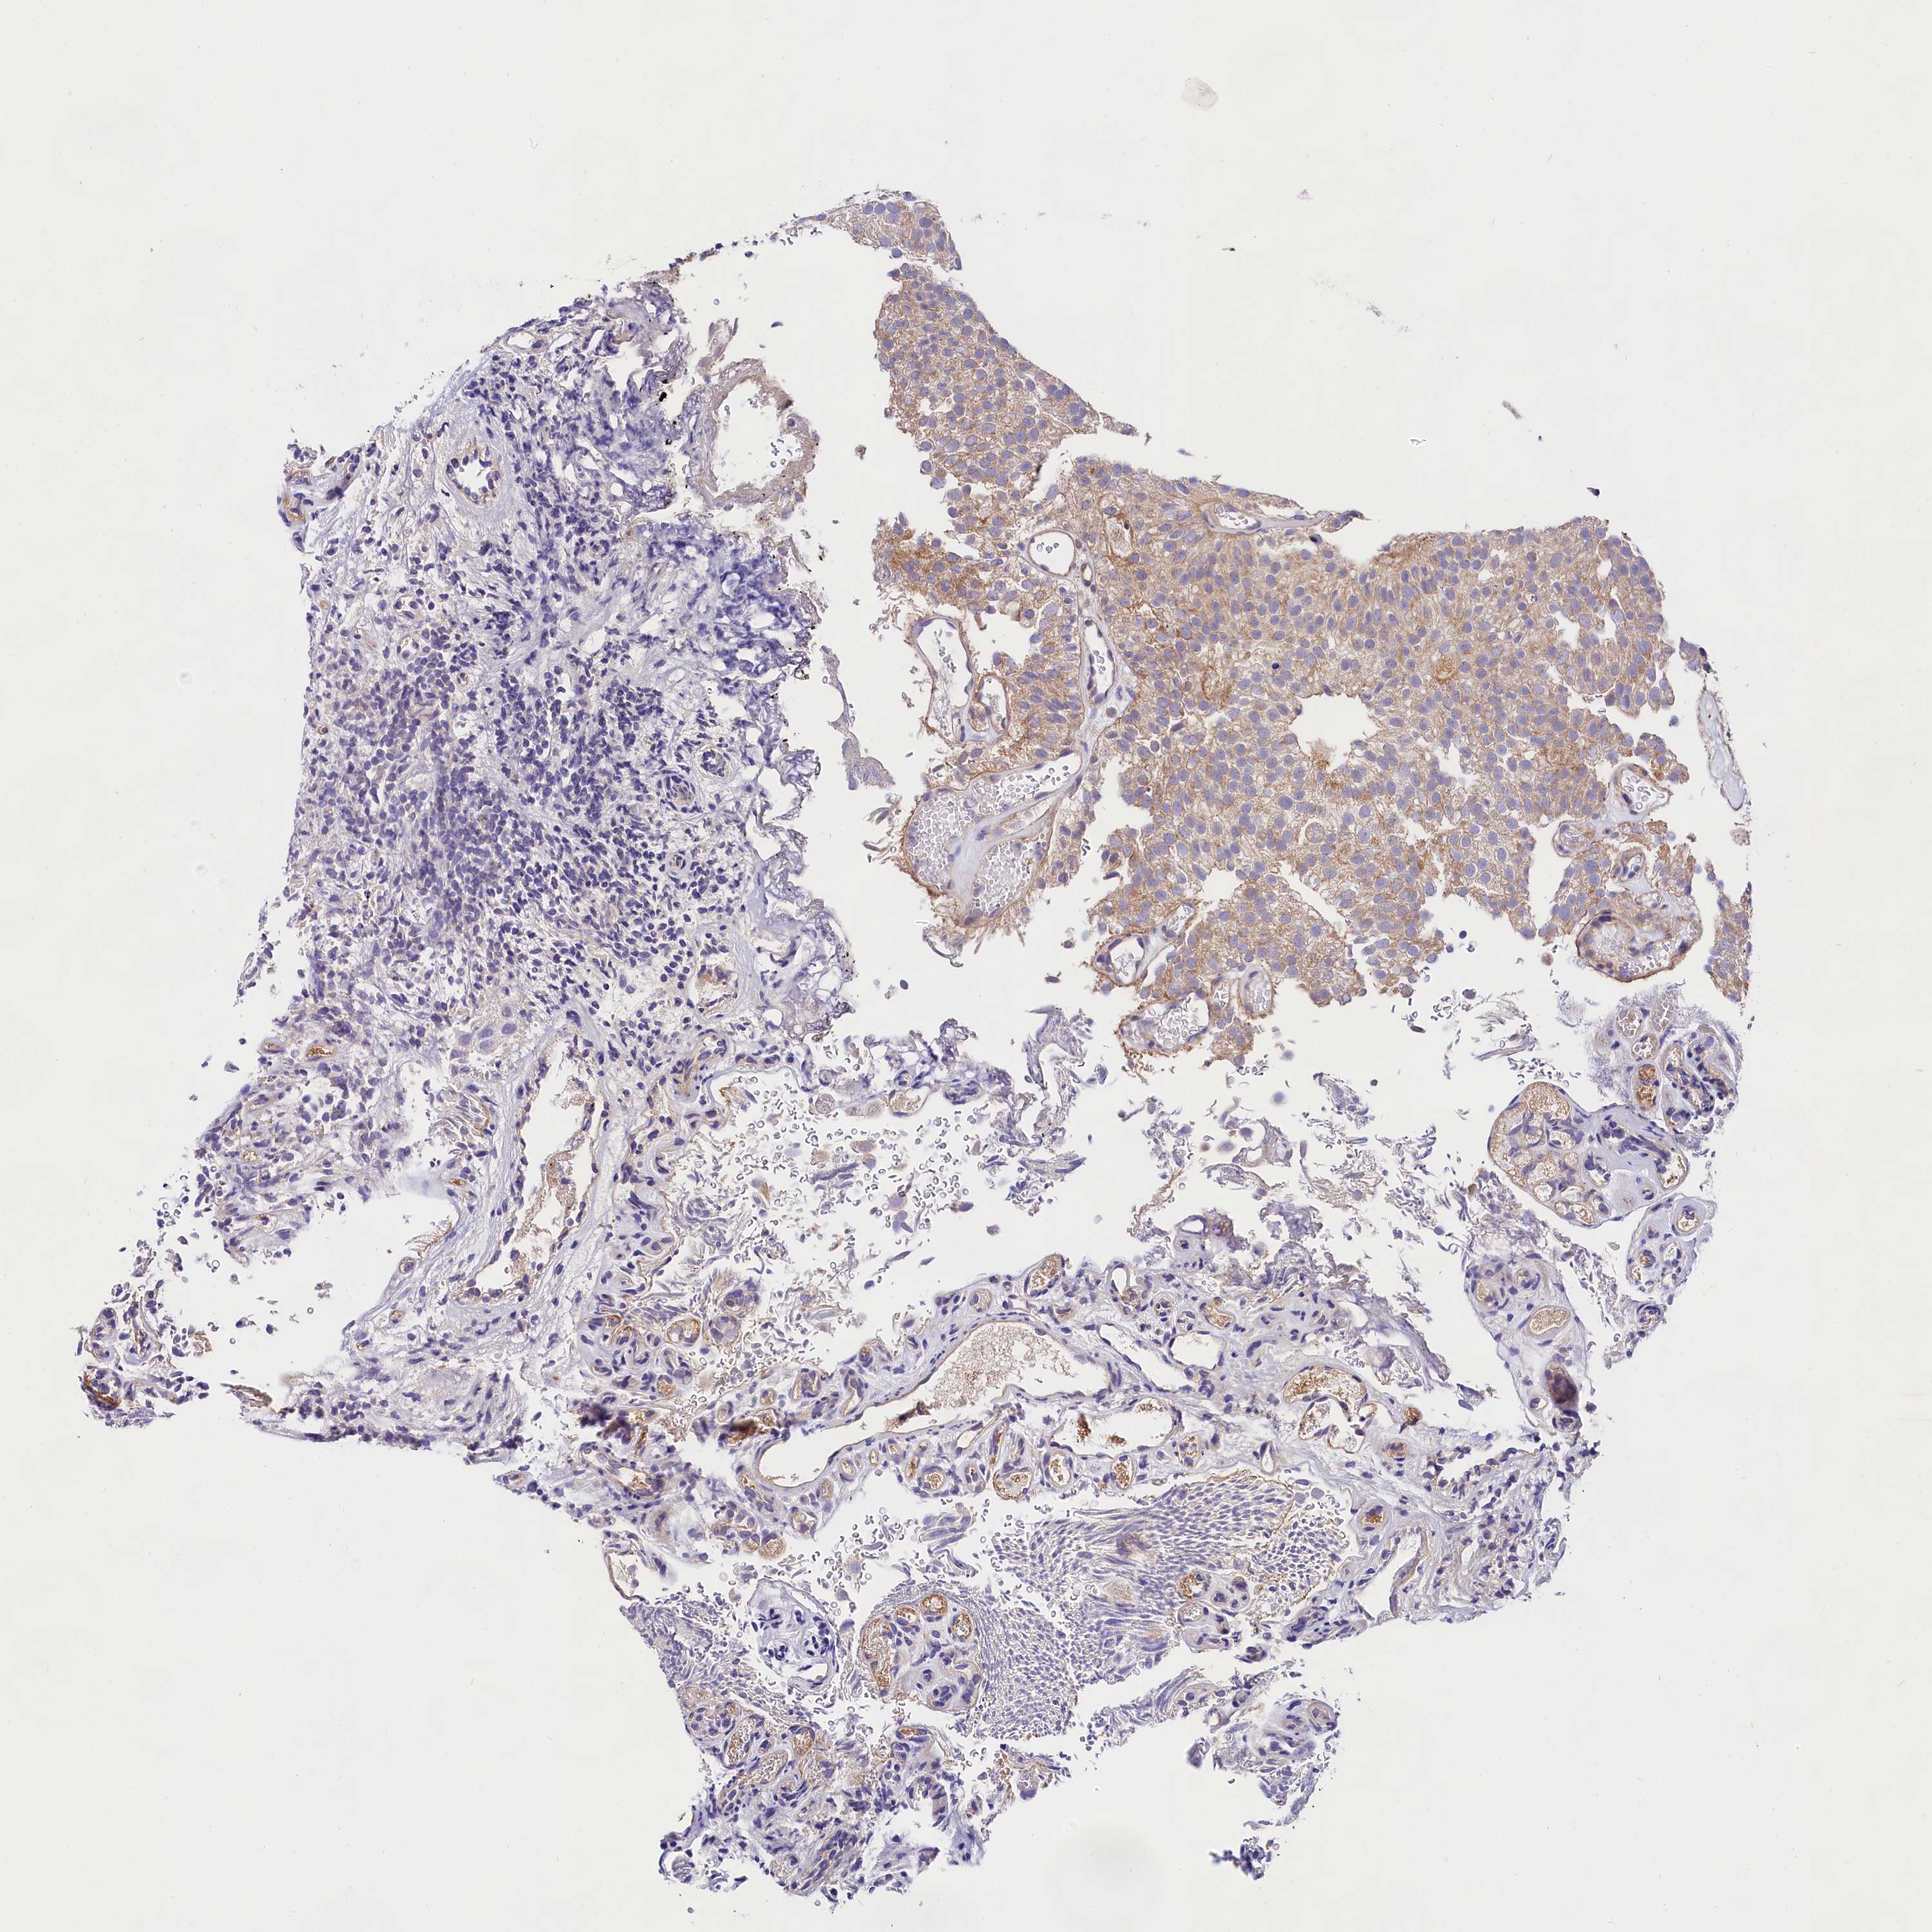

UROTHELIAL CANCER - Protein expressioni

A mouse-over function shows sample information and annotation data. Click on an image to view it in a full screen mode. Samples can be filtered based on level of antibody staining by selecting one or several of the following categories: high, medium, low and not detected. The assay and annotation is described here.

Note that samples used for immunohistochemistry by the Human Protein Atlas do not correspond to samples in the TCGA dataset.

Antibody stainingi

Antibody staining in the annotated cell types in the current human tissue is reported as not detected, low, medium, or high, based on conventional immunohistochemistry profiling in selected tissues. This score is based on the combination of the staining intensity and fraction of stained cells.

Each image is clickable and will lead to virtual microscopy that enables deeper exploration of all samples and also displays staining intensity scores, fraction scores and subcellular localization as well as patient and tissue information for each sample.

Antibody HPA040412

Antibody HPA040947

Urothelial carcinoma, High grade

Urothelial carcinoma, Low grade